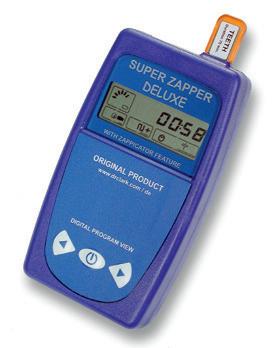

Was ist Hyperthermie genau und wie funktioniert sie? Es ist schon lange bekannt, dass Krebszellen hitzeempfindlicher sind als gesunde Zellen. Werden sie auf 41 bis 43 Grad Celsius erwärmt, sterben bereits viele von ihnen ab. Helmut Knorr und Volkmar Wirth arbeiten seit März 2009 mit einem hochmodernen Gerät zur Anwendung der sogenannten lokoregionalen Tiefenhyperthermie. Es erzeugt elektrische Felder, die das Tumorgewebe auf 41 bis 43 Grad erwärmen. Diese Wärmeanwendung erzeugt folgende Wirkungen:

l Die Krebszellen werden empfindlicher für zytotoxische Effekte, die Resistenz der Krebszellen gegen gewisse Chemotherapeutika kann ausgelöscht werden. Dadurch entfaltet die Chemotherapie eine signifikant stärkere Wirkung. Diese Wirkungssteigerung durch die Hyperthermie ist auch für die Strahlentherapie nachgewiesen.

l «Magnetische» Wirkung: simultan verabreichte Chemotherapeutika werden während der Hyperthermie zum Tumorgewebe hingelenkt, was die Wirkung der Chemotherapie ebenfalls erhöht.

Wenig Nebenwirkungen

Wichtig dabei ist, dass die mittels Hyperthermie erzeugte Erwärmung selektiv, das heisst nur im Tumorgewebe erfolgt. Das angrenzende gesunde Gewebe kann die Wärme durch eine stärkere Durchblutung leicht ableiten und hält seine Temperatur bei rund 37 bis 38 Grad Celsius. Diese Fähigkeit hat das Tumorgewebe aufgrund seiner primitiveren Blutversorgung verloren. Die gestörte Blutzirkulation im Tumorgewebe führt zu einer unzureichenden Wärmeregulierung und damit zu einem Hitzestau, sodass die Wärme ihre

Anwendung der lokoregionalen Tiefenhyperthermie gesammelt. «Sie ist eine gut untersuchte und vielversprechende Methode», so die beiden Oberärzte. «InvivoStudien haben gezeigt, dass der Effekt der Strahlentherapie durch die Hyperthermie um den Faktor 1,2 bis 5 verstärkt werden kann.» Sie sehen diese Resultate durch ihre Erfahrungen in der Praxis bestätigt. Dennoch sei die Hyperthermie keine Wunderwaffe, sondern einfach ein wichtiger und vielversprechender Mosaikstein in der gesamten Krebsbehandlung. u